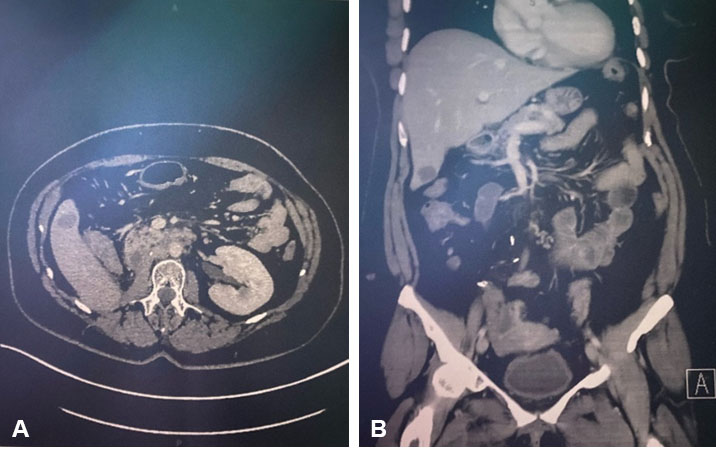

A 25-year-old African-American male was brought to Howard University Hospital as a trauma activation. The patient was described as being found with a facial laceration. At the scene, he was reported to be opening his eyes and moving all extremities when aroused. His car was noted to have multiple bullet holes in it. On primary survey, he was hemodynamically stable, his airway patent, breath sounds were clear bilaterally, and he had 2+ radial and dorsalis pedis pulses bilaterally. His GCS was 11; he was noted to be opening his eyes spontaneously, making incomprehensible sounds, and localizing to pain. On secondary survey, he had a 1 cm wound to the right supraorbital region with minimal bleeding. Other findings included vomitus around his mouth and decorticate posturing of his right upper extremity with normal movement of all other extremities. A non-contrast computed tomogram (CT) of the head demonstrated multiple hyperdense foreign bodies along a path from right to left involving the right supraorbital region, the right frontal lobe, and the left parietal lobe with involvement of the genu of the corpus callosum and left caudate. Scant blood was also noted in the lateral ventricular system and there were hemorrhagic changes in the left caudate nucleus as well as subarachnoid blood in the left sylvian fissure. A fracture of the inner and outer table of the skull with entry into the right frontal sinus was also identified as the bullet entry site.

D.L. returned to our Emergency Department 18 days post-discharge with headaches. He had full motor function of all extremities and was able to hold a conversation with minimal pauses between words. A CT scan of the head done revealed no interval changes compared to the post-operative scan. He was discharged home on oral analgesics and scheduled for a follow-up with the neurosurgeon. Over two subsequent follow-up visits at two and four weeks post-operatively, the patient had completely returned to normal neurologic and normal speech function. He remains on levetiracetam.